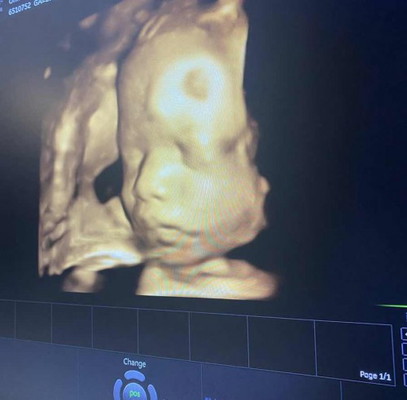

29+5 นน. 1393 กรัม คิดถึงลูกทุกวันเลยย

แม่ๆคนไหนเป็นไหมคะ ไม่เคยเจอหน้ากันแต่นั่งมองภาพซาวด์ แล้วก็คิดถึงมากๆ อยากเห็นทุกวันเลย ❤️❤️

รู้สึกอยากให้ออกมาเร็วๆ อยากหอม อยากกอด อยากฟัดดดด🤭